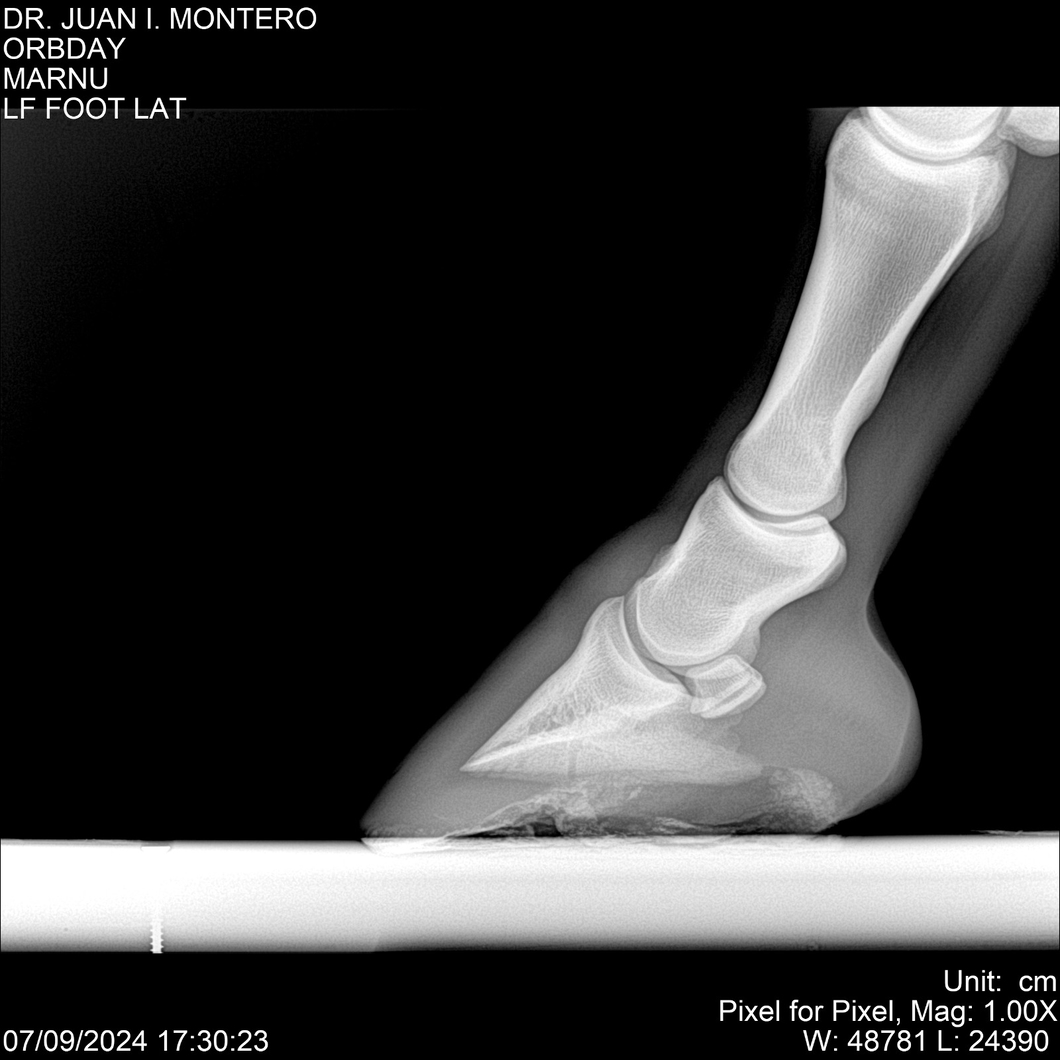

• Empresa: Abelenda N. R., Walter Hugo